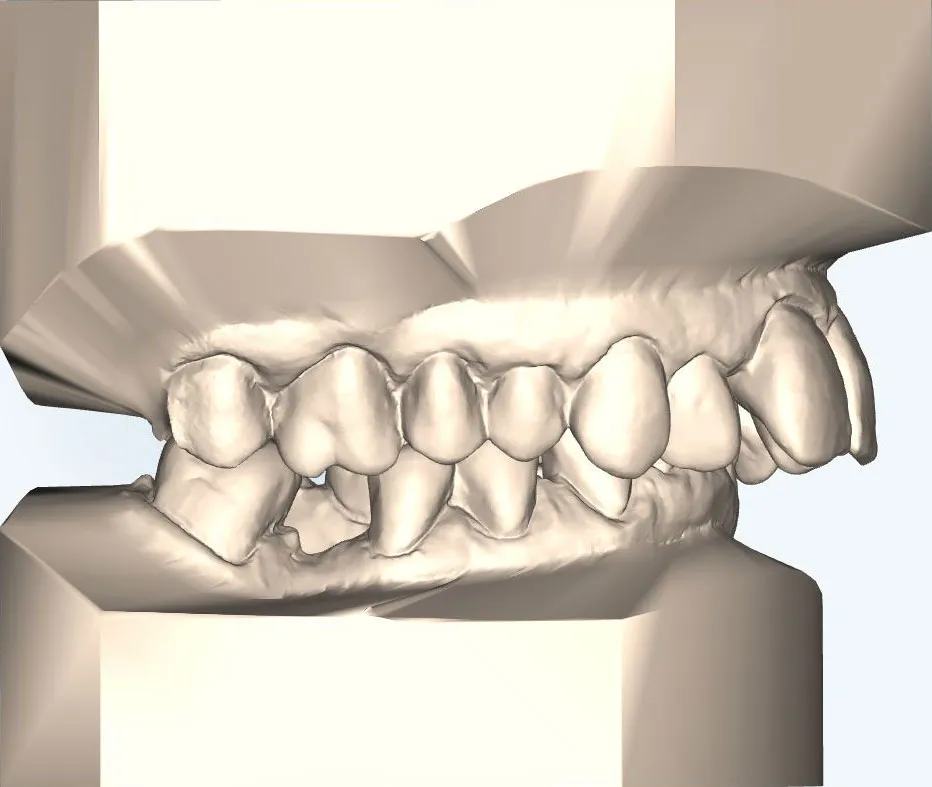

Für die kieferorthopädische Vor- und Nachbehandlung verwenden wir festsitzende Zahnspangen, die während und nach der Operation getragen werden müssen.

Für Patienten, die eine unauffällige Lösung bevorzugen, bieten wir die linguale Zahnspange an:

- Sie wird auf der Innenseite der Zähne befestigt und ist von außen nahezu unsichtbar.

- Die lingualen Zahnspange erzielt durch ihre Individualisierung und ihrer lingualen Position eine sehr effiziente Kraftübertragung im Vergleich zur klassischen, festen Zahnspange – dabei ist sie zudem deutlich diskreter.